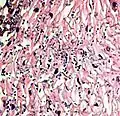

_PAS_stain.jpg.webp)

_PAS_stain.jpg.webp)

A severe case of candidiasis

A severe case of candidiasis